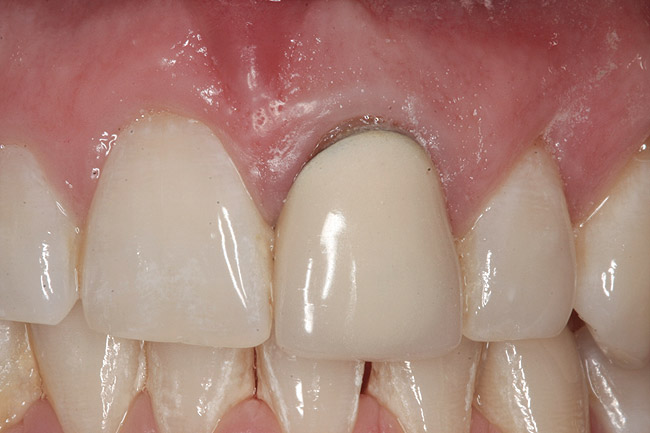

Custom healing abutment in place, with blanching present upon insertion.

Figure 9

Figure 9 shows a custom healing abutment in place; notice the blanching present upon insertion. This reflects the amount of tissue slumping that existed in the short time it took to fabricate the custom healing abutment. An advantage of this type of healing abutment is that it allows a removable provisional restoration to be made for the patient. The main shortcoming of the removable type of provisional, however, is that the soft-tissue support gained from the pontic is only present while the provisional is worn, making this approach highly dependent on patient compliance. If the patient leaves the provisional out for extended periods of time or loses it, the soft tissue will no longer be held in the proper relationship. By having the custom healing abutment underneath the removable prosthesis, the soft tissues are always being held in the proper position. It can also be used under bonded provisionals as well.